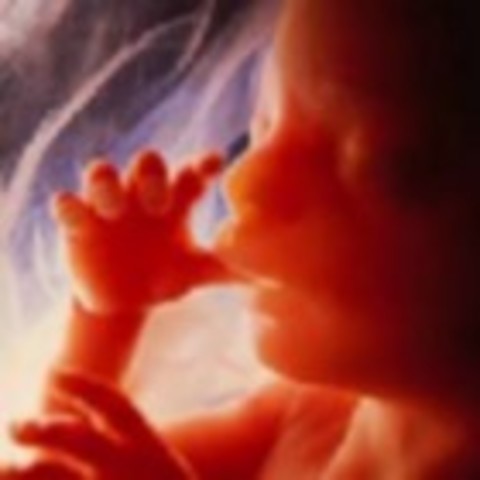

• Week Twelve: Fingernails and Toenails Appear

Week Twelve: Fingernails and Toenails Appear

The pancreas starts to function and produce insulin. The baby's fingernails and toenails appear and they are able to suck on thier thumbs and hiccup.

• Week Thirteen: Baby Flexes and Kicks

Week Thirteen: Baby Flexes and Kicks

Ribs are starting to appear and bones are replacing cartilage. The baby is able to open and close their mouth.